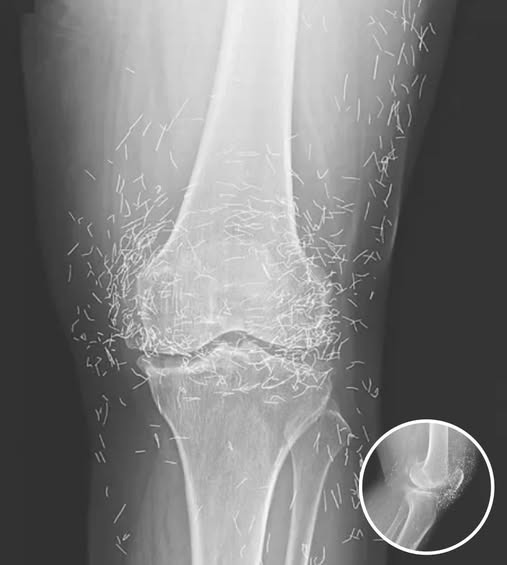

A recent case in South Korea has highlighted the potential risks associated with acupuncture, a traditional therapy used to relieve pain and treat various health conditions. Doctors were shocked to…